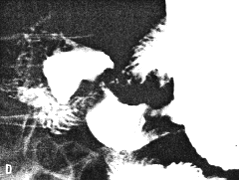

Case 33.8 J.P., 39 year old male. Radiology: 5.0cm long constricting pyloric filling defect. Smooth, concave indentation base of duodenal bulb (Fig. 33.8). Operation: Entire lesser curvature of stomach, part of greater curvature and pyloric region infiltrated. Serosal spread, lymph node and probable liver metastases. Duodenum appears normal. Billroth II. Gastric histology: well differentiated adenocarcinoma with widespread infiltration of gastric submucosa and mucosa. Duodenal histology: spread into submucosa and to lesser extent into mucosa of proximal 2.0 cm of duodenum.

![]() | |

| Fig. 33.8 A-D. Case J.P. Constricting pyloric filling defect. Smooth, concave indentation base of duodenal bulb. | |